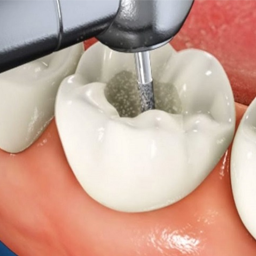

충치 제거

감염된 치아 조직을 완벽하게 제거